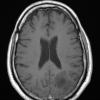

Astrocytoma, IDH-mutant, WHO Grade 2 (3)